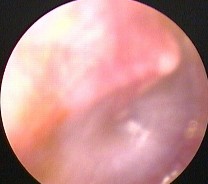

Hình ảnh nội soi tai

Ảnh 8 MN lõm, vàng MSBA. 1912331936 | |